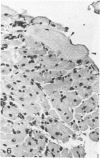

In male BALB/c mice aged 5-6 weeks inoculated three times at intervals of 15 days with 1 X 10(7) epimastigote forms of the PF strain of Trypanosoma cruzi and challenged 30 days after the last inoculation with 2 X 10(4) trypomastigote forms of the Colombia strain of T cruzi (the mice were sacrificed 80-100 days after the challenge) a cardiomyopathy very similar to that observed in the chronic phase of Chagas' disease in man develops. The cardiac syndrome is characterized grossly by cardiomegaly with hypertrophy, dilatation of ventricular chambers, and thinning of the apex of the left ventricle (apical aneurysm) and microscopically by focal areas of myocytolytic necrosis and myocardial degeneration with an inflammatory response composed of mononuclear cells (predominantly macrophages and a few lymphocytes) with concurrent interstitial fibrosis and occasional myofibers containing pseudocysts. In addition, aggregated platelets and occlusive thrombi were found in small epicardial and intramyocardial vessels of infected mice as compared with controls. The potential role of intravascular platelet aggregation in the causation of focal myocardial necrosis and degeneration and apical aneurysm in experimental T cruzi cardiomyopathy in BALB/c mice is discussed.